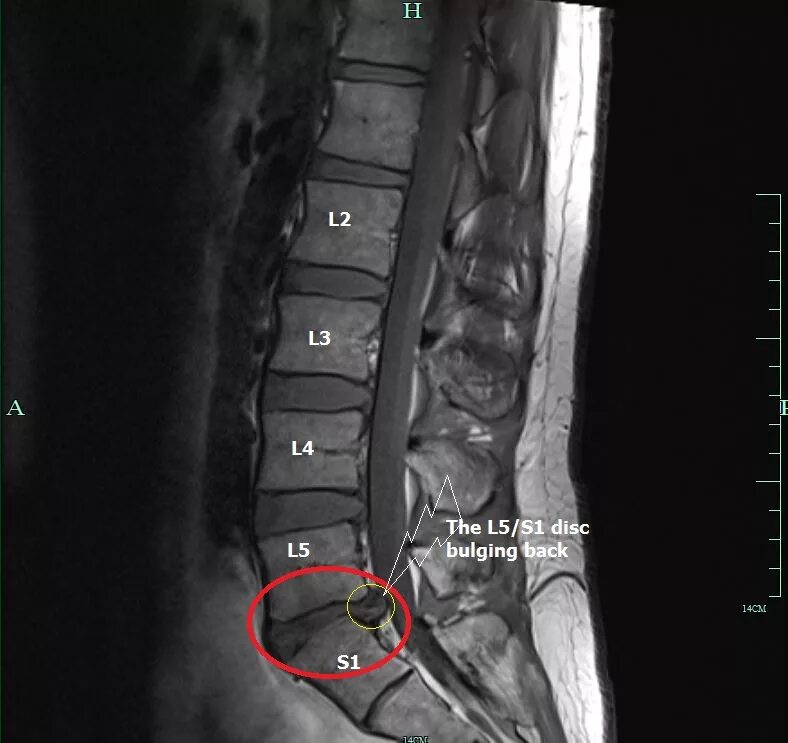

Сегмент l1 l5